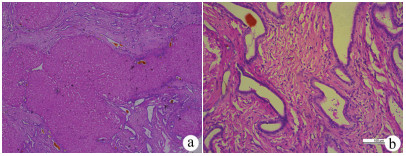

肝癌肉瘤合并肝细胞癌1例报告

李日, 郭怀斌, 梁泽, 李娜, 温军业, 张万星

2021, 37(9): 2180-2182. DOI: 10.3969/j.issn.1001-5256.2021.09.034

摘要(1268) HTML (266) PDF (4255KB)(63)

摘要: